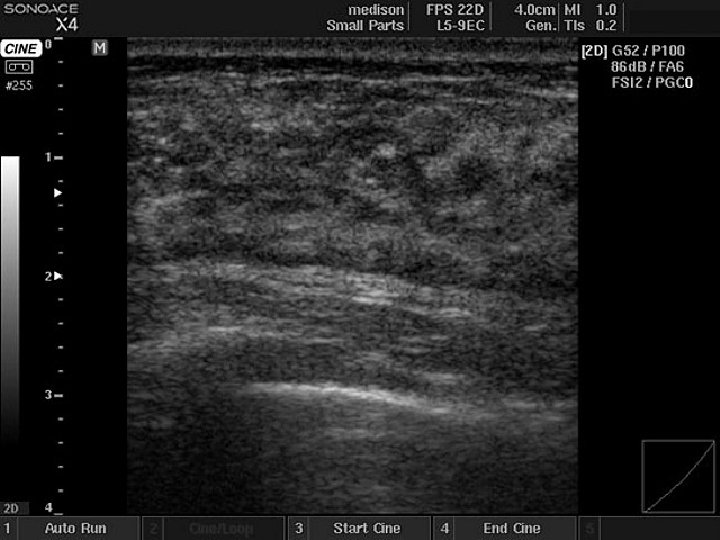

Ultrasound features of benign lumps: Respect tissue plains Long axis horizontal Wall clearly-defined Posterior brightness (cysts) Ultrasound features of malignant lumps Interrupt tissue plains Long axis vertical Wall irregular, poorly-defined Posterior shadowing